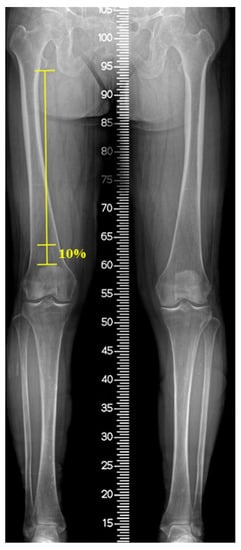

2.3. Radiographic Evaluation

Patients underwent MRI (Magnetom Skyra; Siemens Medical Solutions, Erlangen, Germany) with the knee fully extended in the supine position and stabilized by a knee holder. During MRI, the knee joint (between 1/3rd of the distal femur and 1/3rd of the proximal tibia) was fully covered and contained axial slices of proton density (PD) and PD fat suppression at 2 mm intervals. The VM cross-sectional area (CSA) and the fat infiltration (FI) ratio were measured at the distal 10% level of the femoral length. This level has been previously reported to reflect the total quadriceps volume in patients with knee OA []. The femoral length was defined as the length from the distal end of the lesser trochanter to the superior surface of the patella on a full-length standing anteroposterior radiograph (Figure 2). On coronal MRI view, the level was identified from the superior surface of the patella and the corresponding axial slice was matched using 3D indicators of the picture archiving communication system (PACS; M6, Infinitt Healthcare, Republic of Korea). The VM CSA was acquired from the axial PD image after marking the VM margin using the embedded tools of the PACS software. To assess the FI ratio of the VM, the marked area on the PD slice was transferred to the corresponding PD fat-suppression slice and the intramuscular fat signal within the area was confirmed by comparing the PD and PD fat-suppression slices. Thereafter, the area was color-mapped using 16 different colors for each signal. Color pixels corresponding to the signal of the fat tissue were extracted, and the FI ratio was defined as the percentage of the pixels of the fat tissue to the sum of the pixels of VM (Figure 3). The hip–knee–ankle (H–K–A) angle was determined as the angle formed by the mechanical axis of the femur and the tibia on full-length standing anteroposterior (AP) radiographs. To classify the severity of OA, the tibiofemoral joint was evaluated using the Kellgren–Lawrence scale in standing AP and lateral radiographs as follows: grade I, doubtful narrowing of the joint space and possible osteophytic lipping; grade II, definite osteophytes and possible narrowing of the joint space; grade III, moderate multiple osteophytes and definite narrowing of the joint space; and grade IV, large osteophytes-marked narrowing of the joint space [].

Figure 2.

Measurement of the femoral length (FL), defined as the distance from the distal end of lesser trochanter to the superior surface of patella in full-length standing anteroposterior radiograph.